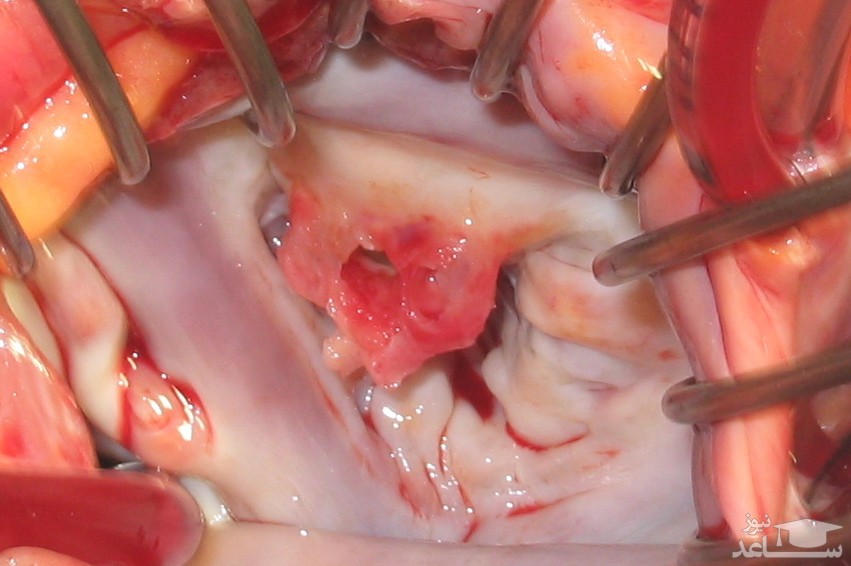

ترمیم دریچه: ترمیم دریچه میترال یک عمل جراحی است که همان دریچه قلب فرد را حفظ می کند. برای اغلب افراد مبتلا به افتادگی دریچه میترال، این روش درمانی جراحی برای تصحیح این وضعیت ترجیح داده می شود. دریچه میترال شامل دو زبانه مثلثی شکل می شود که از جنس بافتی به نام برگچه یا لت تشکیل شده اند. برگچه ها ی دریچه میترال به واسطه ی حلقه ای به نام آنولوس به عضله ی قلب متصل می شوند. جراح می تواند جهت رفع پس زده شدن خون شکل اصلی دریچه را تغییر دهد. (والولوپلاستی) جراحان می توانند از طریق متصل کردن دوباره ی برگچه های دریچه یا با بریدن بافت اضافی دریچه، دریچه را ترمیم کنند تا برگچه ها بتوانند محکم بسته شوند. گاهی اوقات ترمیم دریچه شامل تنگ کردن یا تعویض حلقه ی آنولوس می شود. به این عمل آنولوپلاستی گفته می شود. مهم است تا اطمینان حاصل کنید که جراح شما در ترمیم دریچه میترال تبحر دارد.

تعویض دریچه: در صورتی که ترمیم دریچه ممکن نباشد جراح ممکن است تعویض دریچه انجام دهد. در جراحی تعویض دریچه، دریچه میترال آسیب دیده با یک دریچه ی مصنوعی (از جنس پروتز) تعویض می شود. دریچه های مصنوعی دریچه هایی مکانیکی یا بافتی هستند. دریچه های مکانیکی ممکن است مدت طولانی دوام بیاورند. هر چند که، اگر فرد دریچه مکانیکی داشته باشد، جهت جلوگیری از تشکیل لخته های خون بر روی دریچه باید تا آخر عمر دارویی ضد انعقاد خون مانند وارفارین (کومادین) مصرف کند. اگر یک لخته خون بر روی دریچه تشکیل شود و در جریان خون آزاد شود ممکن است به مغز رفته و سبب سکته مغزی شود.